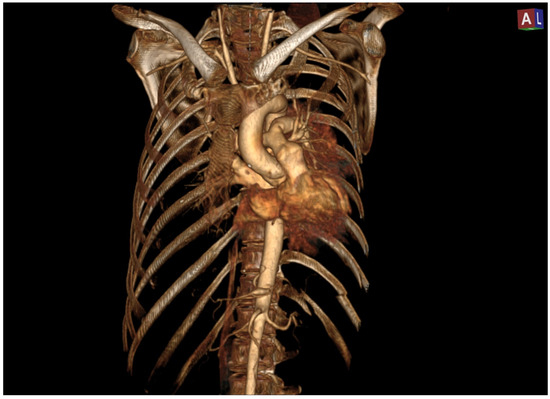

The 3D reconstruction enabled a better visualization of the pericardial damage and the displacement of the heart within the thoracic cavity, which was significantly shifted to the left. (Figure 2).

Figure 2. Three-dimensional reconstruction highlights abnormal position of the heart.